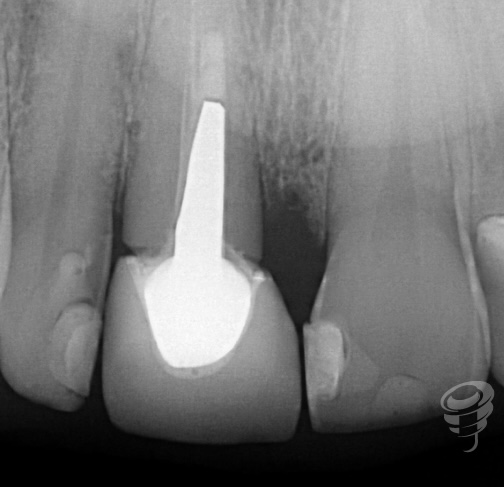

Caso Clínico | Rehabilitación Estética Integral con implante inmediato, injerto óseo y de tejido conectivo y carillas de cerámica en incisivo central superior fracturado

- Caso clínico: Paciente masculino de 45 años con fractura irreparable del incisivo central superior derecho (11) previamente tratado con una endodoncia y unión colado, fracturado por trauma oclusal. Se realizó extracción atraumática, colocación de implante inmediato, injerto óseo xenogénico mezclado con hueso antólogo del fresado, e injerto de tejido conectivo subepitelial para optimizar el perfil de emergencia. A los 4 meses se colocó corona implanto-soportada de zirconio y carillas de disilicato de litio en dientes 12 y 21.

Este reporte describe la rehabilitación integral de un incisivo central fracturado mediante implante inmediato Galimplant IPX 0412, injerto óseo y de tejido conectivo, y carillas de cerámica, con seguimiento a 24 meses.

Figura 1